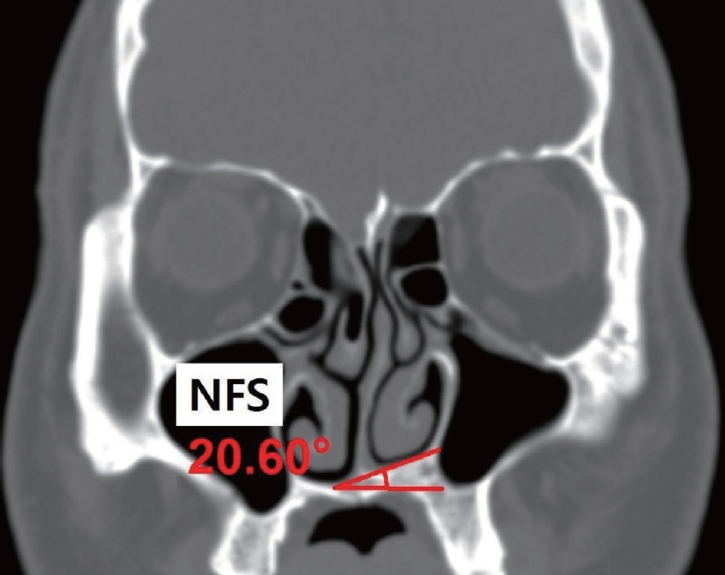

Measurement of NFS and the nasofacial skeletonThe measurement of NFS and other nasofacial skeleton structures were in the cross-section coronal CT image where the crista gali was visualized was visualized (Fig. 2). First, the most inferior point of the bony nasal floor in each nasal cavity was marked. A horizontal line starting from the marked point was then drawn on either side. Finally, a line connecting the two marked points on each side was made. The angle between the two lines was measured and denoted the ‘NFS angle.’ In addition, the side of the higher nasal floor was investigated. The patients who showed no level difference of the nasal floor (NFS angle ≤2°), were categorized as the ‘nonslanted group’, and those with an NFS angle above 2° as the ‘slanted group.’

NotesAuthor Contribution Conceptualization: all authors. Data curation: all authors. Formal analysis: all authors. Funding acquisition: Marn Joon Park, Yong Ju Jang. Investigation: all authors. Methodology: Marn Joon Park, Yong Ju Jang. Project administration: Marn Joon Park, Yong Ju Jang. Resources: all authors. Software: Marn Joon Park, Yong Ju Jang. Supervision: Yong Ju Jang. Validation: Marn Joon Park, Yong Ju Jang. Visualization: Marn Joon Park, Yong Ju Jang. Writing— original draft: Marn Joon Park. Writing—review & editing: Marn Joon Park, Yong Ju Jang. Fig. 1.A flow-chart of the patient selection, and the number of excluded subjects, elaborated in detail. Fig. 2.A coronal ostiomeatal unit CT image is shown on which the most inferior point of the bony nasal floor in each nasal cavity was marked. A horizontal line starting from the marked point was then drawn on either side. Finally, a line connecting the two marked points on each side was made. The angle between these two lines was measured and denoted the ‘NFS angle.’ In addition, the side of the higher nasal floor was investigated. NFS, nasal floor slanting. Fig. 3.Measurement of the nasofacial structures. A: Measurement of nasofacial skeletal structures using an OMU CT image. The IOr base and IMS base were marked on both sides. In a similar fashion to the NFS measurement, the angle between these two lines, the ‘NSD angle,’ was measured. The most protruded point of the bony nasal septum was marked, and the angle formed by the lines from the marked point to the center of the cribriform plate and maxillary crest was calculated. B: Facial photograph of the same patient in the OMU CT scan. C: To investigate the horizontal level asymmetry of the face, the lateral canthus, the most inferior point of the alar base, and the lateral angular margin were marked on both sides. In the same manner as the NFS angle measurement, a horizontal line was drawn on one point, and a line connecting both landmarks was then drawn. The angle between these two lines were measured, and was defined as A1–3, representing the upper, middle, and lower face, respectively. The patient was considered to have a horizontal facial asymmetry when the A1, A2, or A3 angle showed slanting, i.e. was above 0°. D: The presence of an external nose deviation was determined when the angle between the nasion-tip and the nasion-glabella line was above 0° (A4). OMU, ostiomeatal unit; IOr, most inferior point of the orbit; IMS, most inferior point of the maxillary sinus; NFS, nasal floor slanting; NSD, nasal septal deviation. Fig. 4.Linear regression analysis on the degree of nasal floor tilting and the degree of asymmetry of the bony nasofacial structures (n=265). A: A significant positive correlation was observed between the IOr angle and NFS angle. B: A significant positive correlation was observed between the IMS angle and NFS angle. C: A significant negative correlation was observed between the bony NSD angle and NFS angle. IOr, most inferior point of the orbit; NFS, nasal floor slanting; IMS, most inferior point of the maxillary sinus; NSD, nasal septal deviation. Fig. 5.Frontal photograph and ostiomeatal unit CT image of a 22-year-old male patient showing a higher location of the orbit and maxillary sinus on the right side, in addition to a smaller maxillary sinus on the right side, which was the side of a higher nasal floor. Additionally, the lateral canthus margin and the lateral lip margin presented more superiorly on the right side, whereas no level difference was observed in the alar base levels. Table 1.Patient demographics (n=265) Table 2.NFS and its correlation with nasofacial characteristics